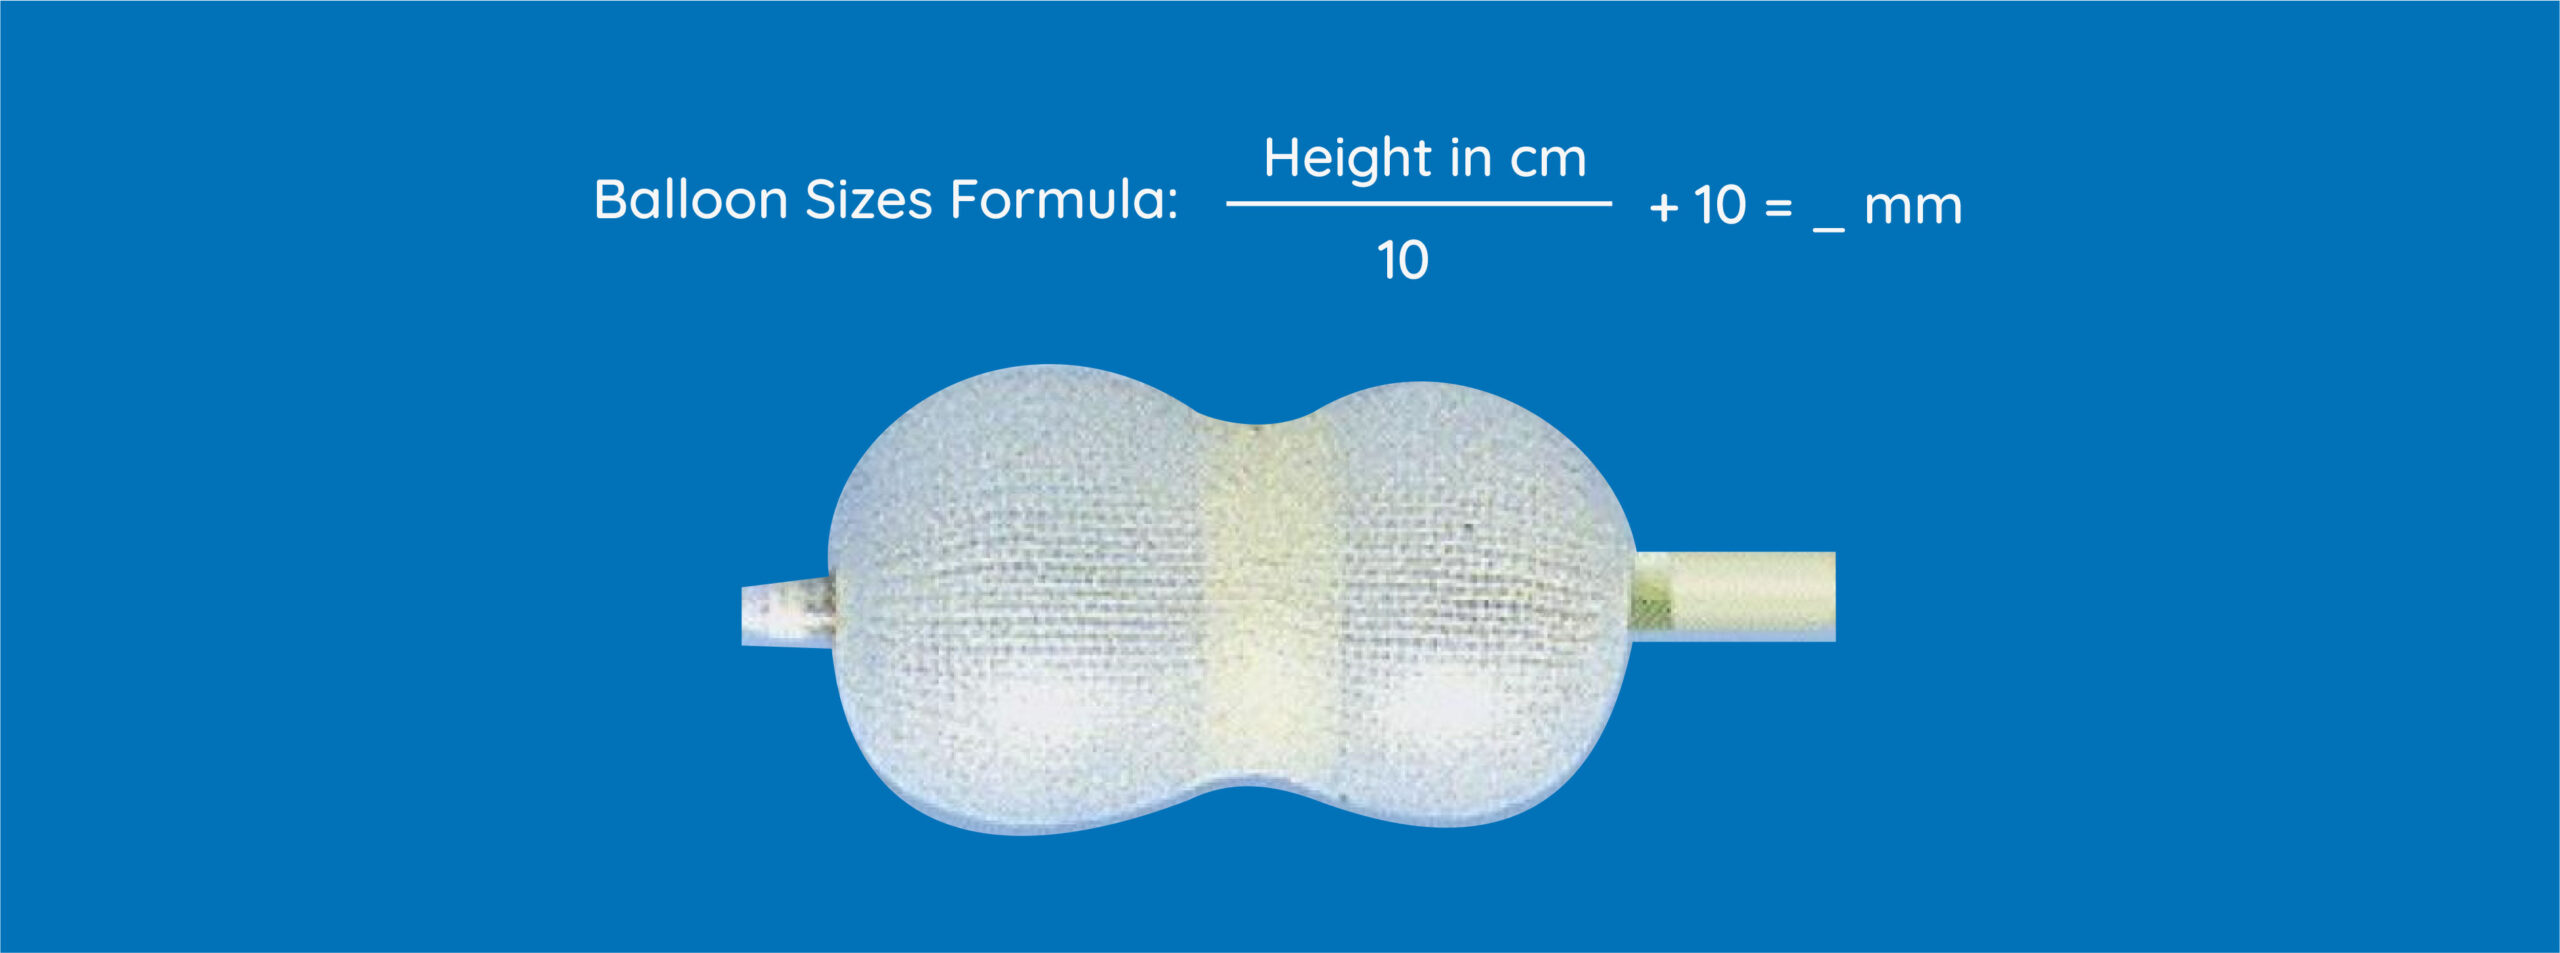

PBMV Balloon Catheter

SYM PBMV Balloon is specially designed to treat mitral valve stenosis.

Features

- Specially Designed balloon, Perfectly shaped to the mitral valve.

- A CE marked product

- Soft and small tip to avoid chances of perforations

- Made of Latex material for increased flexibility to ensure easy inflation and deflation.

- Longer length LA guidewire to increase safety in taller patients.

- 3rd Lumen for extra safety.

- Three Layer for better strength and support

- Economical prices